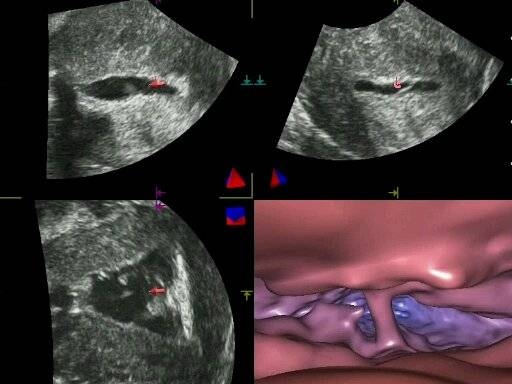

Desde el principio de este año se publicaron varias nuevas técnicas de exámenes ginecológicos, utilizando imágenes virtuales de órganos reproductivos femeninos. Lo que diferencia estas nuevas técnicas de las conocidas anteriormente es que no se precisa ni la exposición de la paciente a los rayos X ni la inyección intravenosa de sustancias conocidas como medios de contraste. Por lo cual se pueden considerar completamente inocuos con respecto a la integridad del ADN de los óvulos y al riesgo de las eventuales reacciones adversas de las pacientes a la inyección intravenosa de los medios de contraste. Con respecto a las técnicas convencionales (no virtuales), estas nuevas técnicas generan el mismo tipo de imágenes de cavidades corporales pero sin necesidad de introducir instrumentos dentro de las respectivas cavidades. Consecuentemente se trata de exámenes indoloros, que no necesitan ni anestesia ni sedación. Este tipo de exámenes, llamados de endoscopia virtual, se han utilizado para analizar cavidades y canales de diferentes órganos reproductivos femeninos, y su esfera de aplicación sigue aumentando.

En un artículo publicado en la revista estadounidense Journal of Gynecology and Women’s Health, el autor de dichas técnicas, el doctor Jan Tesarik de la Clínica MARGen de Granada, resume la aportación de la endoscopia virtual al diagnóstico ginecológico del futuro. Hoy día es posible sustituir la histeroscopia convencional con la histeroscopia virtual, un examen que no necesita anestesia ni sedación y se puede realizar en tan solo 5-10 minutos. La histerosalpingografía convencional, un examen utilizado para evaluar la permeabilidad de las trompas (conductos que comunican los ovarios con la cavidad uterina) se puede también sustituir con un examen ecográfico, llamado histerosalpingoscopia virtual. La posibilidad de sustituir la cistoscopia convencional (examen de la cavidad de vejiga urinaria) con una cistoscopia virtual está actualmente en curso de evaluación.

Todas las técnicas mencionadas representan una alternativa a técnicas endoscopicas directas, que necesitan la introducción de instrumentos dentro de las cavidades examinadas. Sin embargo, las posibilidades de la endoscopia virtual sobrepasan este cuadro. De hecho, endoscopia virtual se puede utilizar para evaluar las cavidades corporales que no están accesibles a un examen endoscópico directo. Este es el caso de la observación de embriones recién implantados en el útero y de la búsqueda de óvulos dentro de los folículos de ovarios bajo estimulación hormonal. La primera de las dos técnicas, llamada embrioscopia virtual, acaba de ser publicada, y la segunda está actualmente en un estadio de ensayos clínicos.

El doctor Jan Tesarik, director de la Clínica Margen de Granada, quien a desarrollado todas estas técnicas junto con la doctora Raquel Mendoza-Tesarik de su clínica y con el doctor Nicolás Mendoza de la Universidad de Granada, comenta: “Las técnicas que estamos introduciendo en el diagnóstico ginecológico tienen varias ventajas en comparación con los métodos tradicionales. Primero, en casos en los cuales existe una alternativa de endoscopia convencional, las técnica virtuales son mucho menos molestas para las pacientes y no comportan riesgos asociados con la utilización de rayos X en una región tan sensible como la de la pelvis donde residen óvulos, portadores del ADN transmitido a las futuras generaciones. Además, las imágenes generadas por estas técnicas son extraordinariamente precisas y flexibles, permitiendo la visualización de estructuras patologicas en diferentes perspectivas y desde puntos de observación libremente elegibles por el observador, lo que no es el caso de las técnicas endoscópicas convencionales. La posibilidad de entrar virtualmente en cavidades y canales no accesibles a una endoscopia directa representan un otro avance importante".